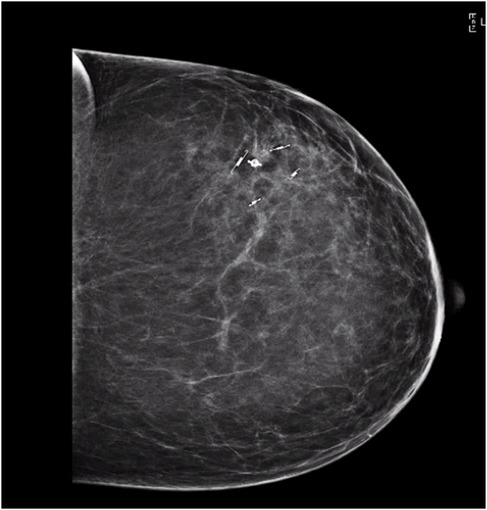

Successful DCIS resection with negative margins on pathology was achieved using SCOUT MD™ localization. With guided feedback from the four unique SCOUT signals, the borders of the non-palpable lesion were clearly identified, and an 18.5 cm × 15.7 cm × 8.5 cm specimen, weighing 430.5 g, was resected from the left breast. A single left axillary sentinel lymph node, identified by radioactive tracer, was removed, ultimately testing negative for any evidence of carcinoma on frozen section. The contralateral right breast reduction and lift was completed by the plastic surgery team, with 900 g of tissue from the benign reduction. Intraoperative tomosynthesis specimen radiograph and imaging confirmed all margins were grossly clear by at least 2 cm around the calcifications. Post-resection imaging of the left breast specimen confirmed the target SCOUT markers at the expected locations proximally, laterally, medially, and distally around the punctate calcifications (Figure 5).

Figure 5. Post-resection ultrasound scan of the mass, identifying the four unique SCOUT reflectors surrounding the punctate calcifications in excised tissue.